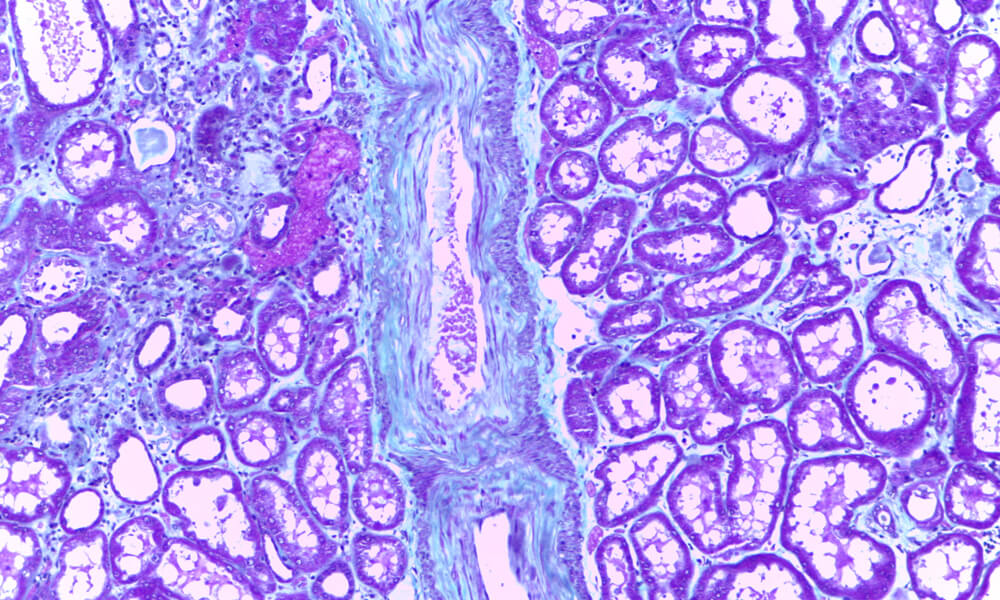

Exames Histológicos

• Exame histológico de biópsias e peças operatórias

Técnicas Complementares de Diagnóstico

• Imunohistoquímica

• Histoquímica